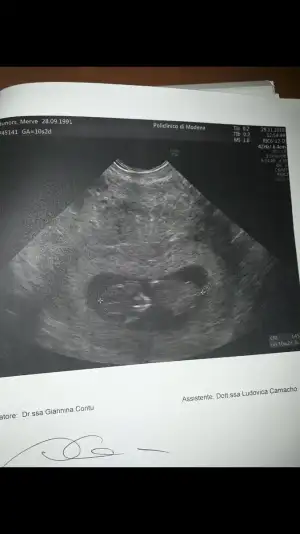

Kizlar bugün kontrolüm vardı annemlerin yanina 1 ayligina geldigim icin yurtdışında muane oldum burda 3.5 aylık olana kadar karindan bakmiolarmis kucuk belli olmuyor diye vajinal muane etti bebegin durusu dikkatimi cekti ters duruyor ilk kez böyle gördüm bebekler böylede ters dururmu ya

Gun icinde kac farkli pozisyonda duruyor bebekler endise etmeyin o an oyle yakalanmis

Evet ama sürekli böyle durmaz döner